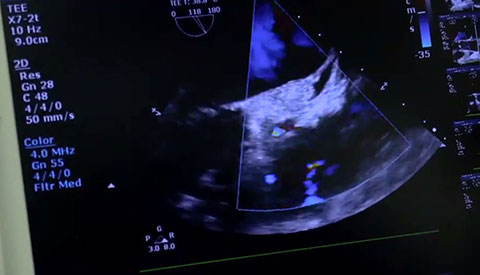

Uw patiënt is gediagnosticeerd met symptomatische aortastenose. Ze is 85 jaar, heeft diabetes en een hoge bloeddruk. U weet dat ze een verhoogd risico loopt en niet in aanmerking komt voor hartchirurgie, maar misschien wel voor transkatheter aortaklepvervanging (TAVR). Vandaag de dag bieden innovatieve beeldvormingsoplossingen en percutane instrumenten hoop voor sommige patiënten die tot nu toe geen andere opties hadden .